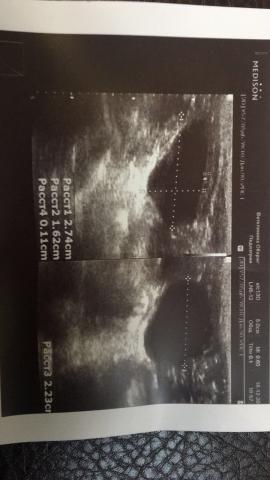

Если можно, то немного подробнее. На основании чего вам поставили такой диагноз, только на основании проведенного УЗИ? Может быть, собаке брали какие-то анализы? Если да, то выложите, пожалуйста, здесь их результаты. Если только данные УЗИ, то это разговор ни о чем (я имею ввиду панкреатит). Гастрит по данным УЗИ вообще не ставят.

К сожалению, ничего не могу рассмотреть. Попробуйте сами прочесть описание с фото. Если сможете, сделайте снимок более качественным. Или можно снять крупнее по частям. Может быть, тогда буквы будут видны более четко.

Спасибо, фотографии четкие. Я все прочитал. Как я и думал, там и "не пахнет" никаким гастродуоденитом, а тем более, панкреатитом.